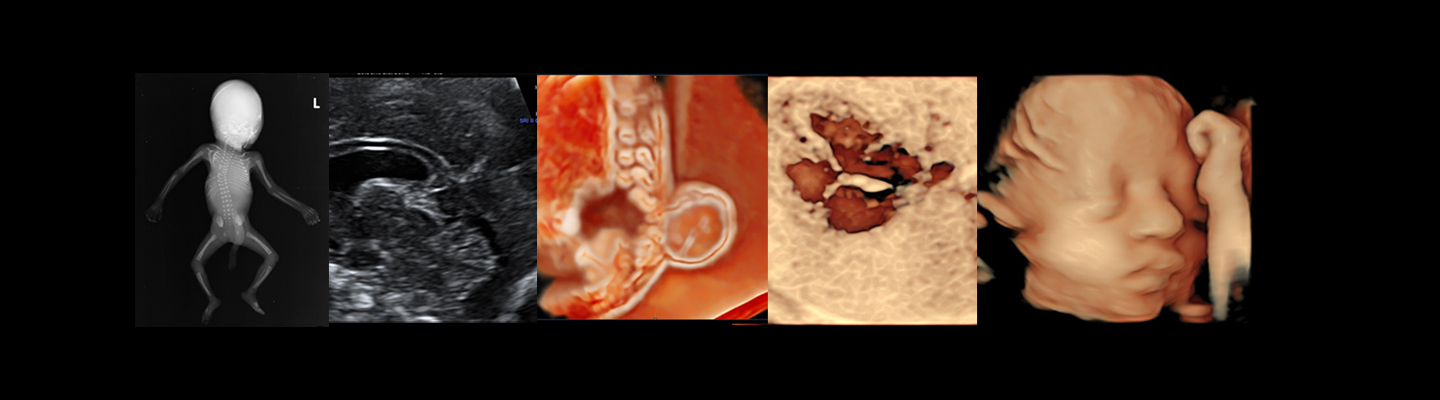

Practicing obstetrics without a knowledge of obstetric ultrasound is near to impossible in the current clinical scenario.

The current postgraduate curriculum does not involve specific training modules or hands on experience on ultrasound training. This course aims to provide adequate training to young Obstetricians and Radiologists to perform Obstetric ultrasound to International standards. This is achieved by a continuous learning process with theory and practical knowledge combined with hands on experience so that they would be able to perform obstetric scans across all gestations with confidence. During this period, they would be given adequate training to obtain the certificates of competencies from the fetal Medicine Foundation UK.

This short-term course is aimed at practising Obstetricians and Radiologists who don’t aspire to specialise in fetal medicine but would like to improve their skills in Obstetric Ultrasound scanning to complement their clinical practice.